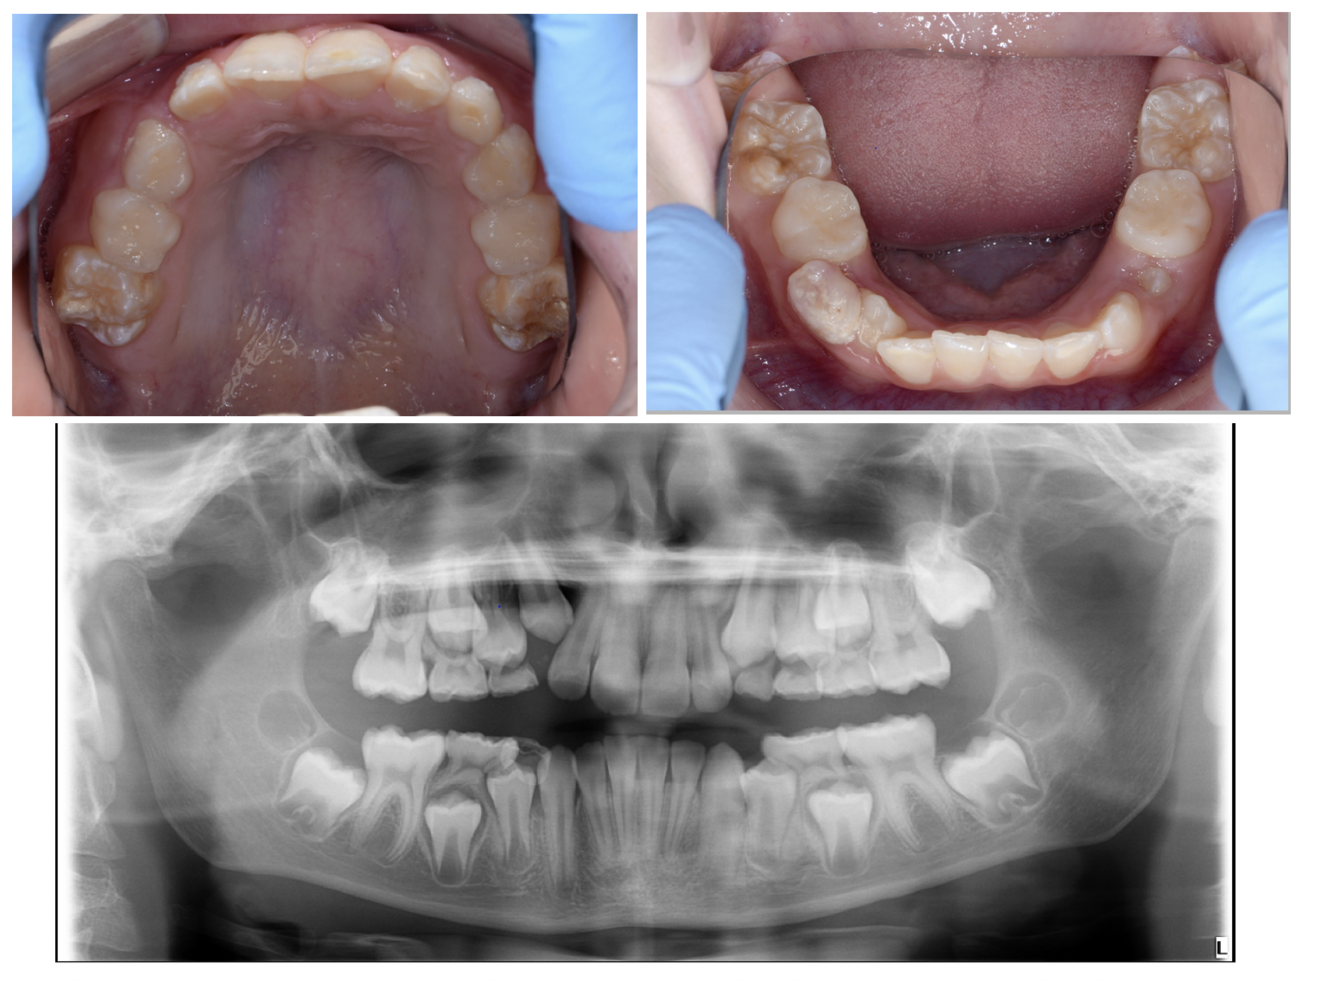

* 8 year old patient * Mom concerned about the extra tooth and child concerned about her teeth appearance * She has type 1 diabetes takes insulin injections (well controlled) From radiograph - caries present What management options can **you** provide for this patient? (4)

* Attempt caries removal for carious lesions on 55,54,64,74,85 and restore with composite, GI , RMGI (need compliance) * If not cooperative enough = SCC of 5's and 4's * If still not cooperative = SDF or non-restorative cavity control to make lesions cleansable * If not cooperative at all = Provide OHI and monitor or sedation under IS or GA

83

* 8 year old patient * Mom concerned about the extra tooth and child concerned about her teeth appearance * She has type 1 diabetes takes insulin injections (well controlled) From radiograph - caries present on primary teeth What treatment can you provide under LA?

* Selective caries removal (possible without)

84

* 8 year old patient * Mom concerned about the extra tooth and child concerned about her teeth appearance * She has type 1 diabetes takes insulin injections (well controlled) From radiograph - caries present What treatment options should be considered for GA?

* Surgical XLA of supernumeraries

96

What are possible reasons for delayed eruption of an upper central incisor? (4)

* Supernumerary teeth * Trauma * Ectopic teeth * Failure of development

97

When would be an appropriate time to investigate the delay eruption of a upper first incisor?

8 years old

98

What are the 4 types of supernumerary teeth? (4)

* Conical * Tuberculate * Supplemental * Odontome

99

Which supernumerary is the most common cause of failed/delayed eruption of an upper permanent central incisor?

* Tuberculate